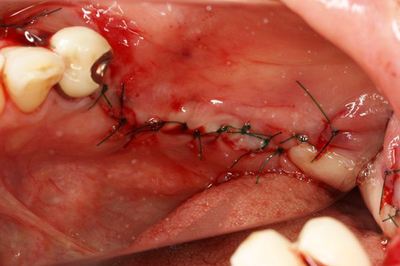

縫合を終えました。

二次手術時に歯肉弁根尖側移動術を行います。